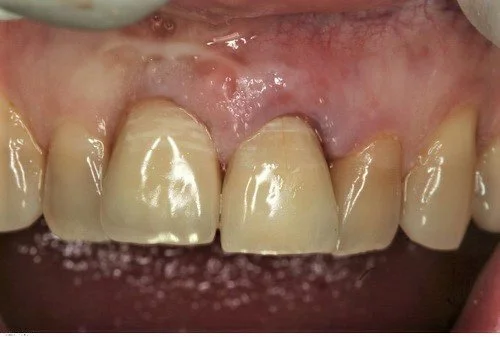

A healthy 40 year old gentleman presented with tooth 21 which was unrestorable due to gross internal resorbtion. He is a non- smoker with excellent oral hygiene.

The photo below shows the post operative result one hour after extraction. Note the relative continued eruption (and alveolar bone growth) of the surrounding dentition compared to implant crown 11 placed 20 years ago. This is a common problem when implants are placed in young patients in the aesthetic zone.